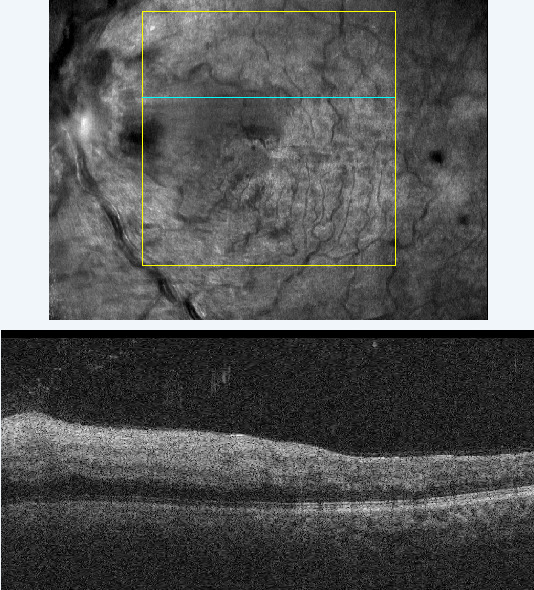

The patient returned 1 month later for a follow-up visit. He reported mild improvement in vision and good compliance with his primary care and hematology visits. His best-corrected vision was 20/50 in the left eye with no improvement on pinhole. Acuity in the right eye was stable at 20/20. Slit-lamp examination was unremarkable in both eyes. Optic nerve head swelling and intraretinal hemorrhages in the posterior segment improved from the initial visit, veins were dilated and tortuous, and the retinal whitening was no longer present. Optical coherence tomography was repeated, which revealed improved retinal edema (Figure 4) with underlying retinal pigment epithelium disruption. Macular change analysis showed improvement of edema at follow-up compared with the initial visit (Figure 5).

A close-up of a landscape AI-generated content may be incorrect.

Figure 4.Optical coherence tomography of the left eye macula at follow-up showing improvement in edema.

A screenshot of a medical scan AI-generated content may be incorrect.

Figure 5.Optical coherence tomography of the left eye macula at follow-up showing resolution of retinal edema on the macular change analysis report.